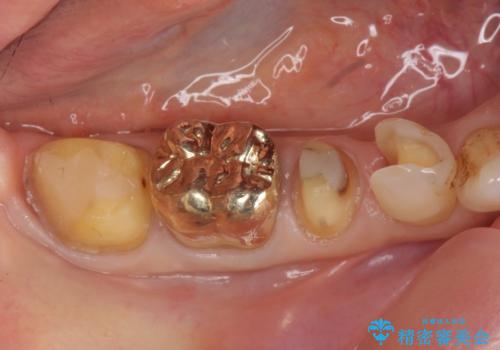

- 右下の古い銀歯のやり替えを希望された方の症例です。

口腔外から見えやすい 4 番目、5 番目の歯はセラミックによる審美的な治療を行い、6 番目、 7 番目の奥歯 2 歯は適合性に優れたPGA(ゴールド)クラウンによる治療を行いました。

PGA(ゴールド)について

ゴールドは化学的な安定性が高いため変色や腐食がほとんどなく、アレルギーなども起こりにくい人体に優しい素材です。

また硬さも天然歯に近いため周囲の歯への影響も少なく、さらに適合もよいため虫歯の再発も少ない、とても補綴に適した材料です。